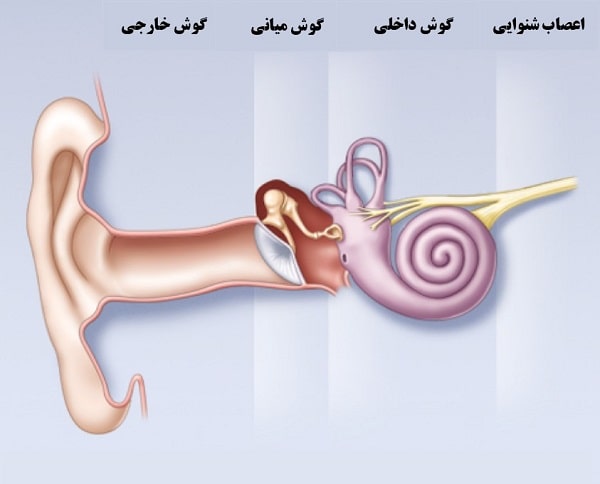

گوش و حلق و بینی